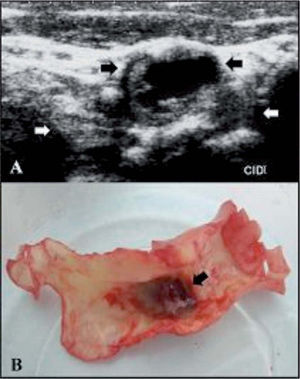

Caso clínico. Pacientes que no pueden encuadrarse en las guíasPresentamos, a modo de ejemplo, un paciente de 67 años con un stroke isquémico frontotemporal derecho y 2 AIT recurrentes en el mismo territorio, separados por tres meses y ocurridos dos años antes de la consulta. Fue evaluado con Holter, monitorización de eventos de 7 días y ecocardiograma transesofágico sin evidencia de fuentes de cardioembolia. Un electroencefalograma prolongado con activación compleja y una polisomnografía descartaron actividad comicial. Dos DVC demostraron una extensa placa en ACI derecha con remodelación positiva y un gran hematoma intraplaca (fig. 6). La estenosis, medida tanto por DVC como por A-RMN, no era mayor del 50%. De acuerdo con las guías de práctica clínica, este paciente no tendría indicación quirúrgica. Sin embargo, dados los signos de vulnerabilidad de la placa y considerando que presentaba recurrencias, a pesar de estar bajo tratamiento médico (aspirina, atorvastatina y enalapril), se decidió realizar una EC.

A: doppler color de vasos del cuello de placa ateromatosa en la arteria carótida interna derecha que evidencia hematoma intraplaca (flechas negras) y remodelación externa (flechas blancas). B: placa resecada mediante endarterectomía carotídea en la que se observa el hematoma recubierto por una muy adelgazada capa fibrosa, que ha sido retraída para una mejor visualización.